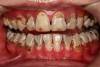

There are several advantages of using SDF in dental treatment. First, it showed an antimicrobial activity against mono-species, dual-species, and multi-species cariogenic biofilm.14-16 Silver ions are bactericidal metal cations that inhibit biofilm formation.17 Studies have indicated that silver interacts with sulfhydryl groups of proteins and DNA, thus altering hydrogen bonding and inhibiting respiratory processes, DNA unwinding, cell-wall synthesis, and cell division.18 At the macro level, these interactions affect bacterial killing and inhibit biofilm formation.17 Second, fluoride promotes caries lesion remineralization. Fluoride has been indicated to react with hydroxyapatite and generate calcium fluoride, which is a reservoir of fluoride, and facilitate further remineralization.19 An ex vivo study reported surface microhardness of the surface layer of the arrested caries after SDF applications was comparable with the unaffected sound dentin20 (Figure 1 and Figure 2). This is consistent with another study, in which a high remineralized zone was observed on the surface of arrested caries from exfoliated teeth with SDF treatment21 (Figure 3 and Figure 4). Third, its application procedures are simple and do not require injection or drilling, and the treatment does not involve expensive support infrastructure equipment such as piped water and electricity. The simplicity of the treatment is conducive to treating caries in apprehensive young children who may have intense dental fear, uncooperative patients with special needs, or elderly patients who have difficulty adapting to traditional dental care. It also allows trained workers to deliver the treatment to people who live in the area but who may not be able to easily access dental service.22 Patient compliance and satisfaction is often good when the patient is provided a clear explanation of the treatment outcome.23,24 Finally, the cost of SDF treatment is low and should be affordable in most communities.

Fig 2. Ground section of a primary incisor with arrested caries lesion after SDF treatment: microhardness of dentin (in median Knoop hardness number) in soft and SDF-arrested caries according to the distance from the lesion surface. (image from Chu and Lo, 2008, ref 20 [reprinted with approval])

Figure 2